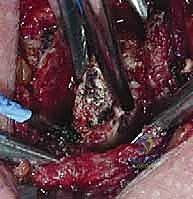

الخطوة 4: إعادة البناء باستخدام الطعوم الوترية (Reconstruction)

بمجرد إزالة العظم، يصبح المفصل غير مستقر. هنا تبرز مهارة الجراح في إعادة بناء الأربطة الممزقة. يقوم الدكتور هطيف بأخذ طعم وتري (غالباً من أوتار الركبة للمريض نفسه - Hamstring graft، أو باستخدام أشرطة صناعية متطورة). يتم حفر ثقوب دقيقة في عظم القص وما تبقى من الترقوة، ويُمرر الطعم الوتري من خلالها بنمط يشبه "الرقم 8" (Figure-of-8) لربط الترقوة بالضلع الأول أو بعظم القص بمتانة فائقة.